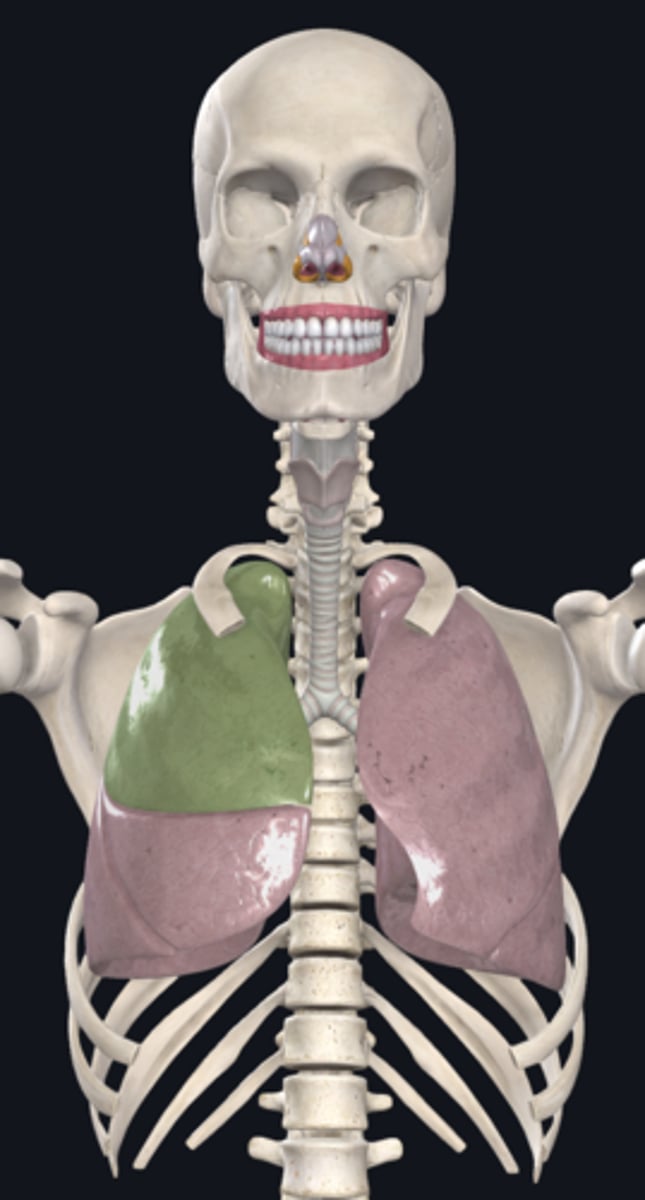

right lung

superior lobe of right lung

middle lobe of right lung

inferior lobe of right lung

left lung

superior lobe of left lung

inferior lobe of left lung

base (diaphragmatic surface)

apex

pulmonary artery

pulmonary vein

hilum of right lung

hilum of left lung

diaphragm